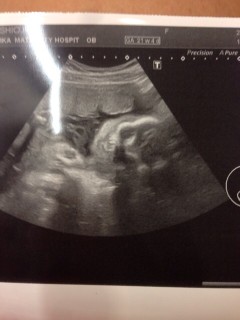

写真:26w0d:ちゃまたろーさん:一卵性双子ちゃん

4Dでは胎盤に隠れちゃって顔見れず、2Dで先生が撮ってくれました

次28wの時がラストチャンスになるので次回が楽しみ

720gと男の子割には小さめなのかな?

毎日元気に動いてくれるのでこのまま順調に成長してほしいです